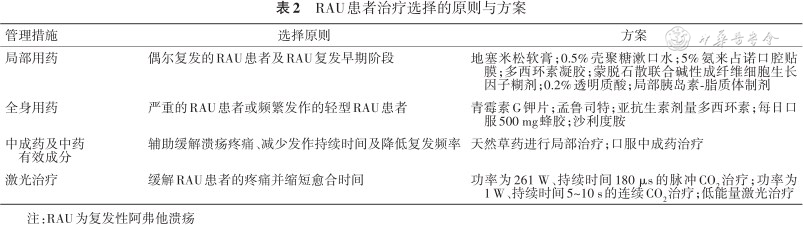

RAU患者的治疗选择原则与方案见表2。

RAU患者治疗选择的原则与方案

RAU患者治疗选择的原则与方案

| 管理措施 | 选择原则 | 方案 |

|---|---|---|

| 局部用药 | 偶尔复发的RAU患者及RAU复发早期阶段 | 地塞米松软膏;0.5%壳聚糖漱口水;5%氨来占诺口腔贴膜;多西环素凝胶;蒙脱石散联合碱性成纤维细胞生长因子糊剂;0.2%透明质酸;局部胰岛素-脂质体制剂 |

| 全身用药 | 严重的RAU患者或频繁发作的轻型RAU患者 | 青霉素G钾片;孟鲁司特;亚抗生素剂量多西环素;每日口服500 mg蜂胶;沙利度胺 |

| 中成药及中药有效成分 | 辅助缓解溃疡疼痛、减少发作持续时间及降低复发频率 | 天然草药进行局部治疗;口服中成药治疗 |

| 激光治疗 | 缓解RAU患者的疼痛并缩短愈合时间 | 功率为261 W、持续时间180 μs的脉冲CO2治疗;功率为1 W、持续时间5~10 s的连续CO2治疗;低能量激光治疗 |

注:RAU为复发性阿弗他溃疡